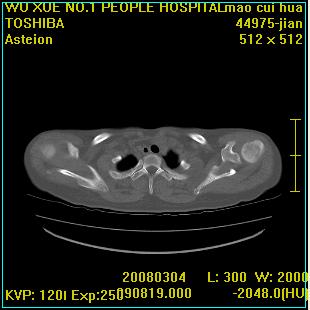

标题: CT12025:男,50岁,左肩活动受限半年。 [打印本页]

标题: CT12025:男,50岁,左肩活动受限半年。

肩关节骨质破坏呈小囊状,其周软组织轻度肿胀,余未见异常。

考虑:肩袖损伤。建议mri。

左侧肱骨头密度不均匀,高低混杂,周围软组织略肿胀,考虑结核性病变。

左侧肱骨头密度不均匀,高低混杂,髓腔密度稍高,周围软组织略肿胀,肌间隙模糊,考虑慢性骨髓炎可能。密切结合临床!